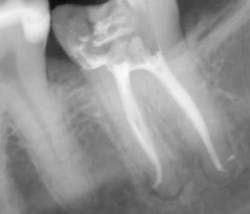

Step 3: Obturate

Canals are carefully dried with paper points. Insert the gutta-percha with AH sealer in the canal to working length, and take it back out. Add additional sealer to the gutta-percha, and then in a gentle pumping motion insert gutta-percha back to working length. Sear off access with a thermal pen and apply gentle pressure with a condenser.

Using a pumping motion and adding additional sealer ensures that voids within the canals get filled. This generates the “puff” effect with small amount of sealer being extruded from the apex of canals. It also helps ensure accessory canals are not left unfilled.